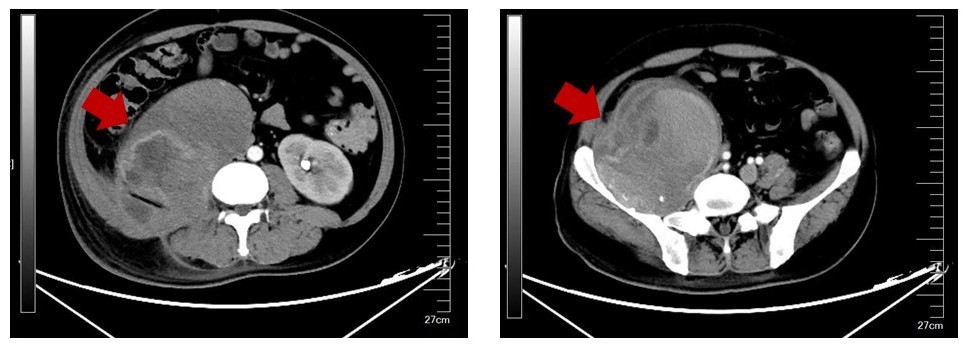

据悉,该患者确诊血友病近20年,病程中逐渐出现腹腔假肿瘤,伴随剧烈腰疼、腹痛、腹胀等症状,且肿瘤持续增大,直径近15公分,压迫右侧腰大肌,导致无法弯腰、行走,严重影响生活质量,进一步发展甚至会危及生命。因血友病患者凝血功能存在先天性缺陷,手术出血风险极高,且腹腔假肿瘤巨大,与周围组织脏器关系密切,手术难度极大,患者辗转多地求医无果,治疗陷入困境。

手术当日,在麻醉科的严密监护下,朱健康教授团队按照既定方案稳步推进。首先请泌尿外科术中放置输尿管支架,保护同侧输尿管等器官。术中探查发现假肿瘤体积巨大,与周围组织粘连严重,且存在大量陈旧性血肿,处理难度极高。团队凭借丰富的临床经验和默契的协作,成功完成肿物切除及周围组织修复,整个过程出血控制理想,手术顺利完成。术后,医护团队密切监测患者生命体征与凝血功能,精准调整抗凝、止血治疗方案,患者恢复平稳,各项指标逐步恢复正常,顺利康复出院。